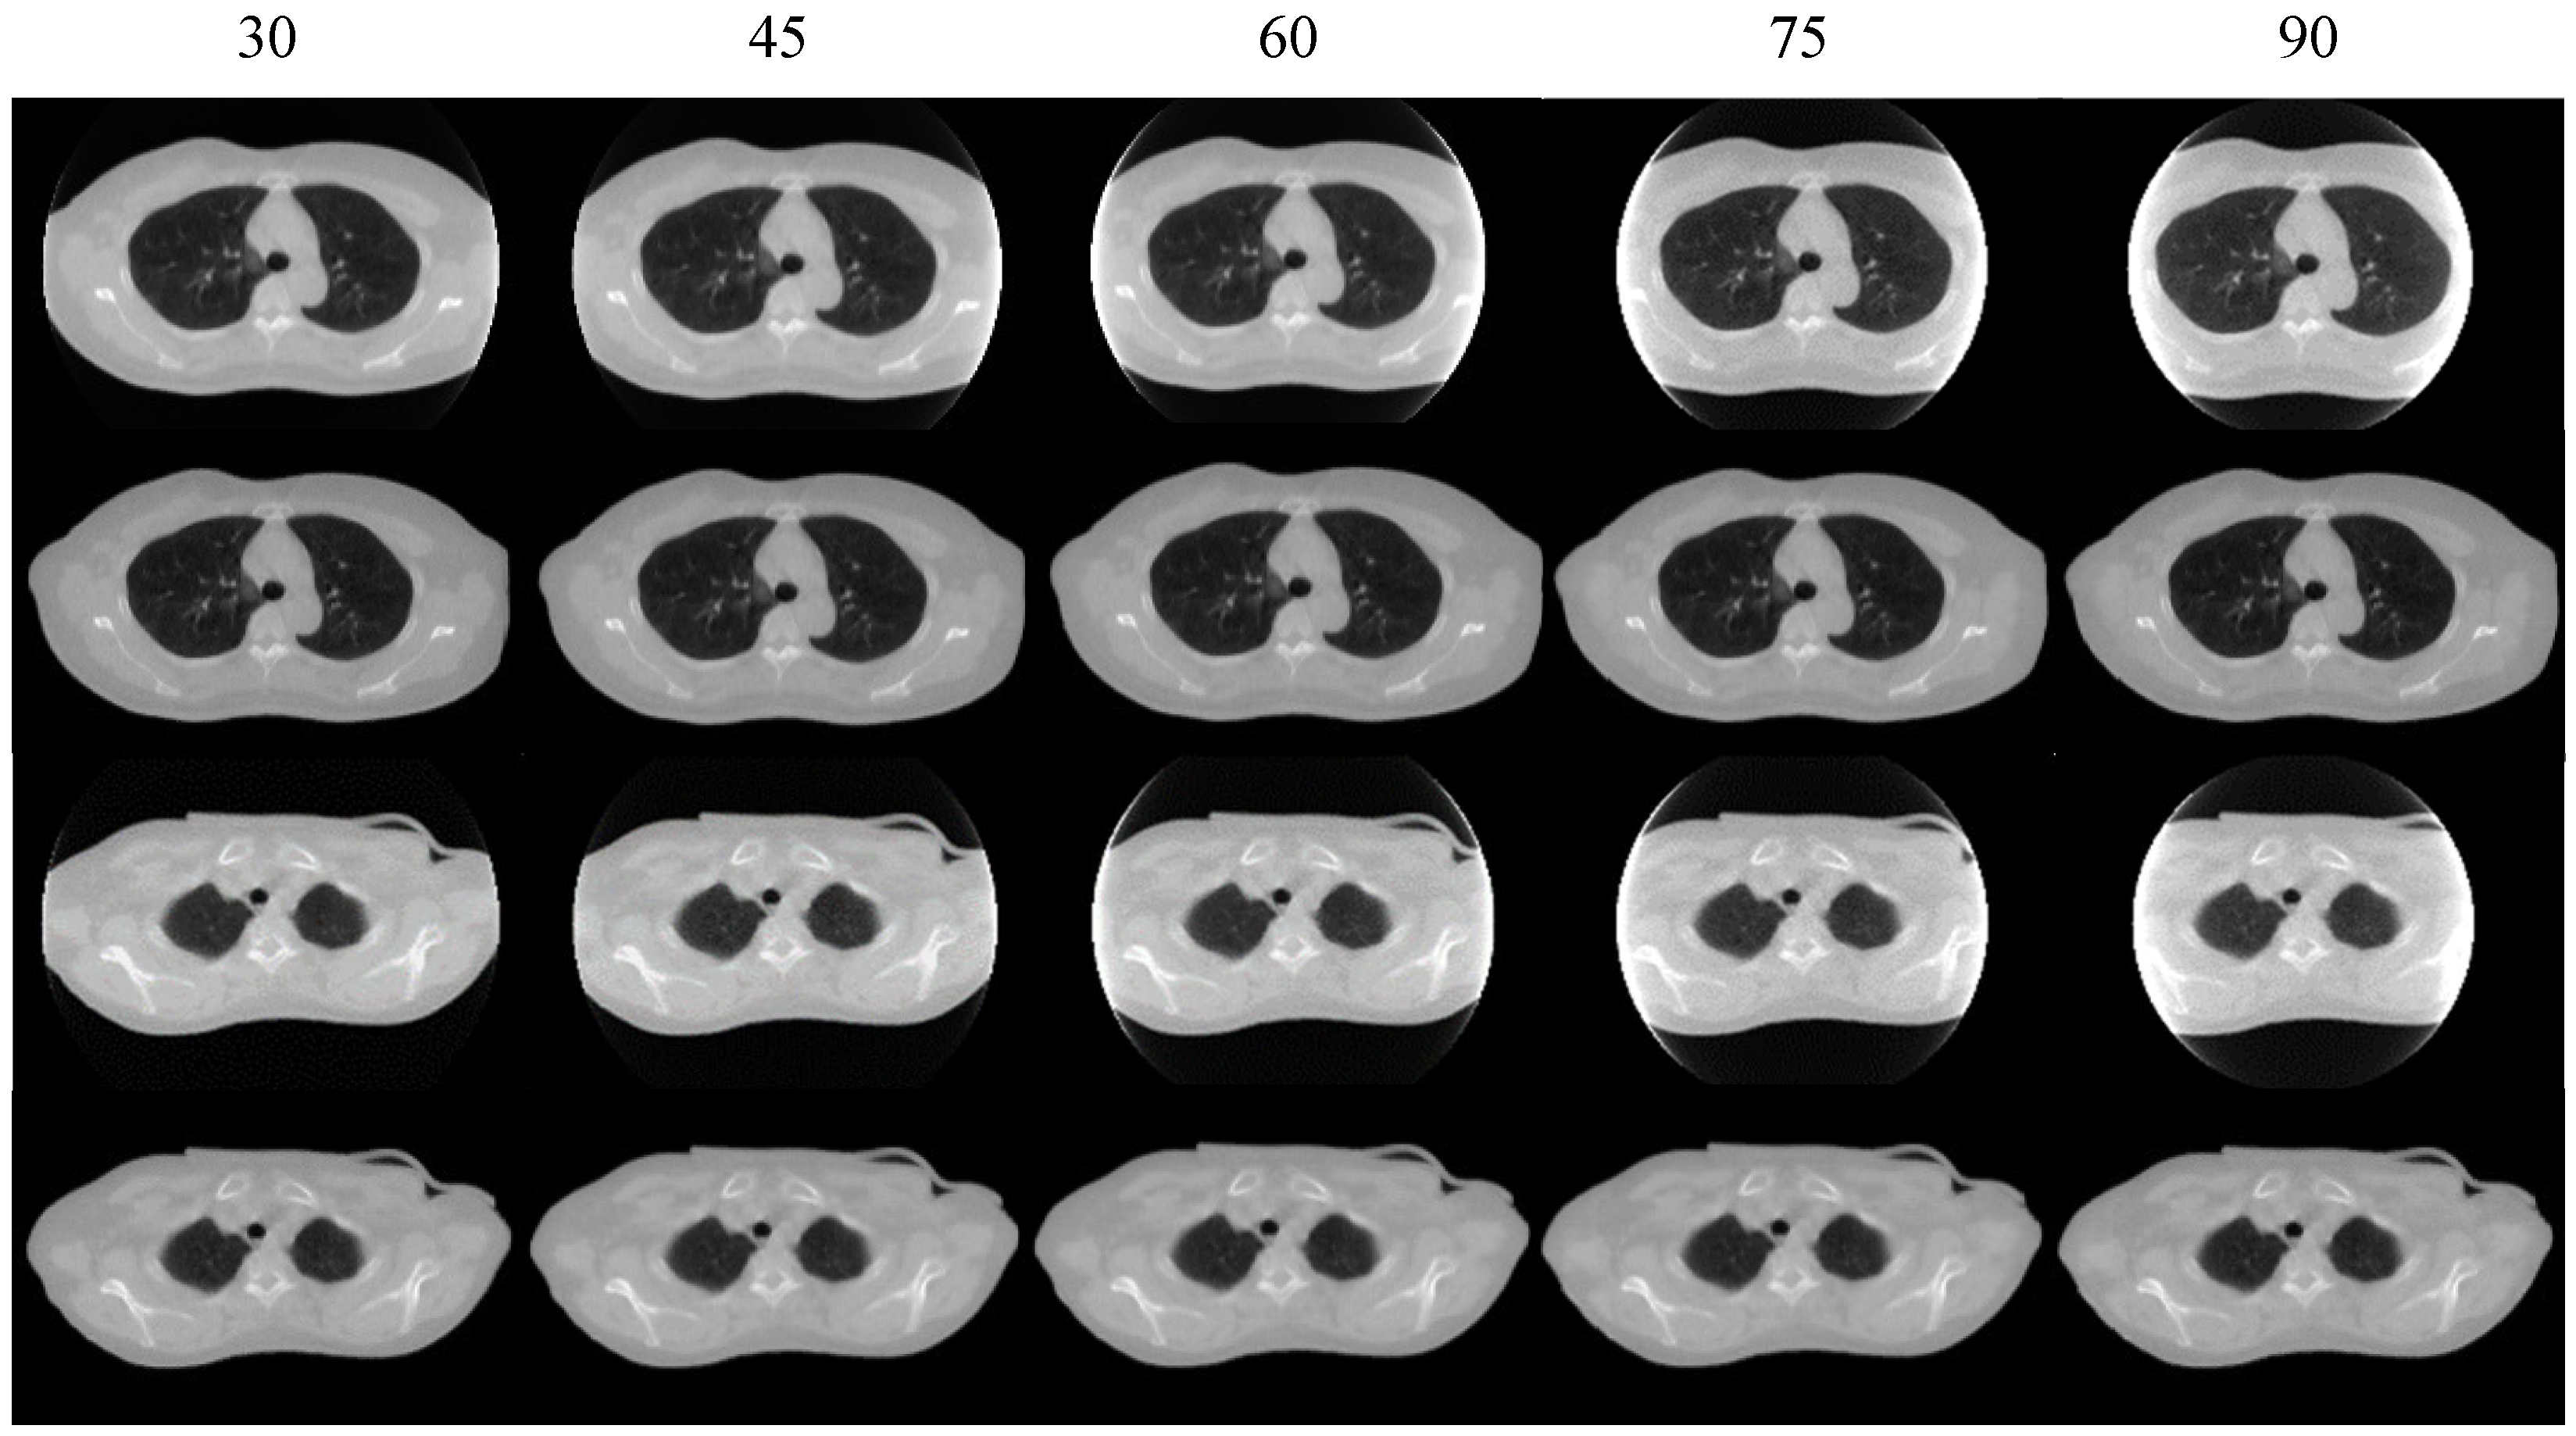

4.4. Ablation Study

| FOVNet (without TransNet) | 45.95 | 107.66 | 94.90 |

| Prior-FOVNet (with TransNet) | 26.49 | 77.00 | 97.18 |